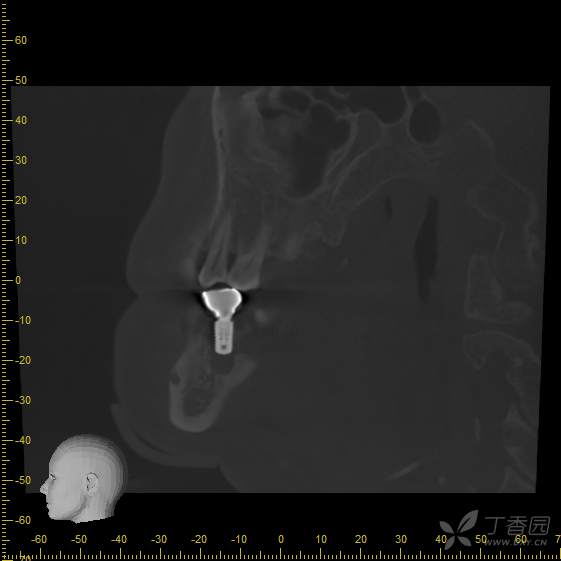

术前cbct,可见36拔牙窝低密度影,牙槽嵴顶骨白线不可见,推理低密度影可能为炎性肉芽组织,矢状位截图,可见牙槽分隔

手术即刻拍摄cbct,手术过程中刮净肉芽组织,碘酊灼烧,大量生理盐水冲洗,植入4.8*8mm骨水平种植体一枚

接诊时,36种植牙松1-2°,颊侧牙龈未见明显红肿。拍摄cbct后可见种植体周骨结合丧失,大量低密度影,骨吸收至根尖1/3,种植体浮出。